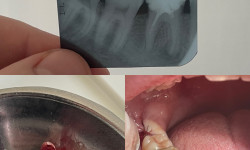

Встановлення зубного імпланту га місці втраченого зуба

Встановлення зубного імпланту — це хірургічна процедура, під час якої в кістку щелепи імплантується титановий гвинт, що виконує функцію кореня зуба. На цей імплант згодом встановлюється коронка, яка імітує натуральний зуб.